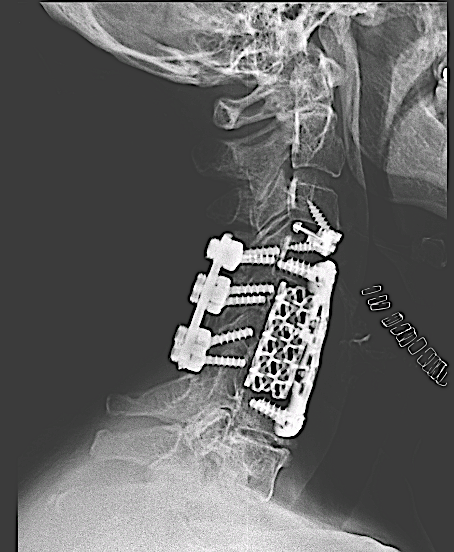

-El desarrollo de las cajas intersomáticas cervicales atornilladas plantea una solución sencilla y óptima bajo mi punto de vista:

- Respecto a la placa cervical: no es necesario retirarla (lo cual ahora bastante trabajo y riesgos si se trata de una corpectomía con injerto tipo malla como el caso que describo a continuación).

- Respecto a la caja intersomática (cage stand alone): su uso puede generar dudas en un nivel adyacente, con mayor exigencia mecánica.

Control postoperatorio